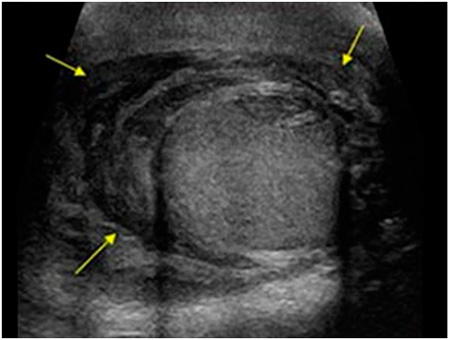

Ábra. Ultrahangos képalkotó piotsele. Mint haematocele körül megjelenő folyadék a tojás nem egyenletes, vannak vékony szálak fibrin, amelyek eredményeként kialakult gyulladás.